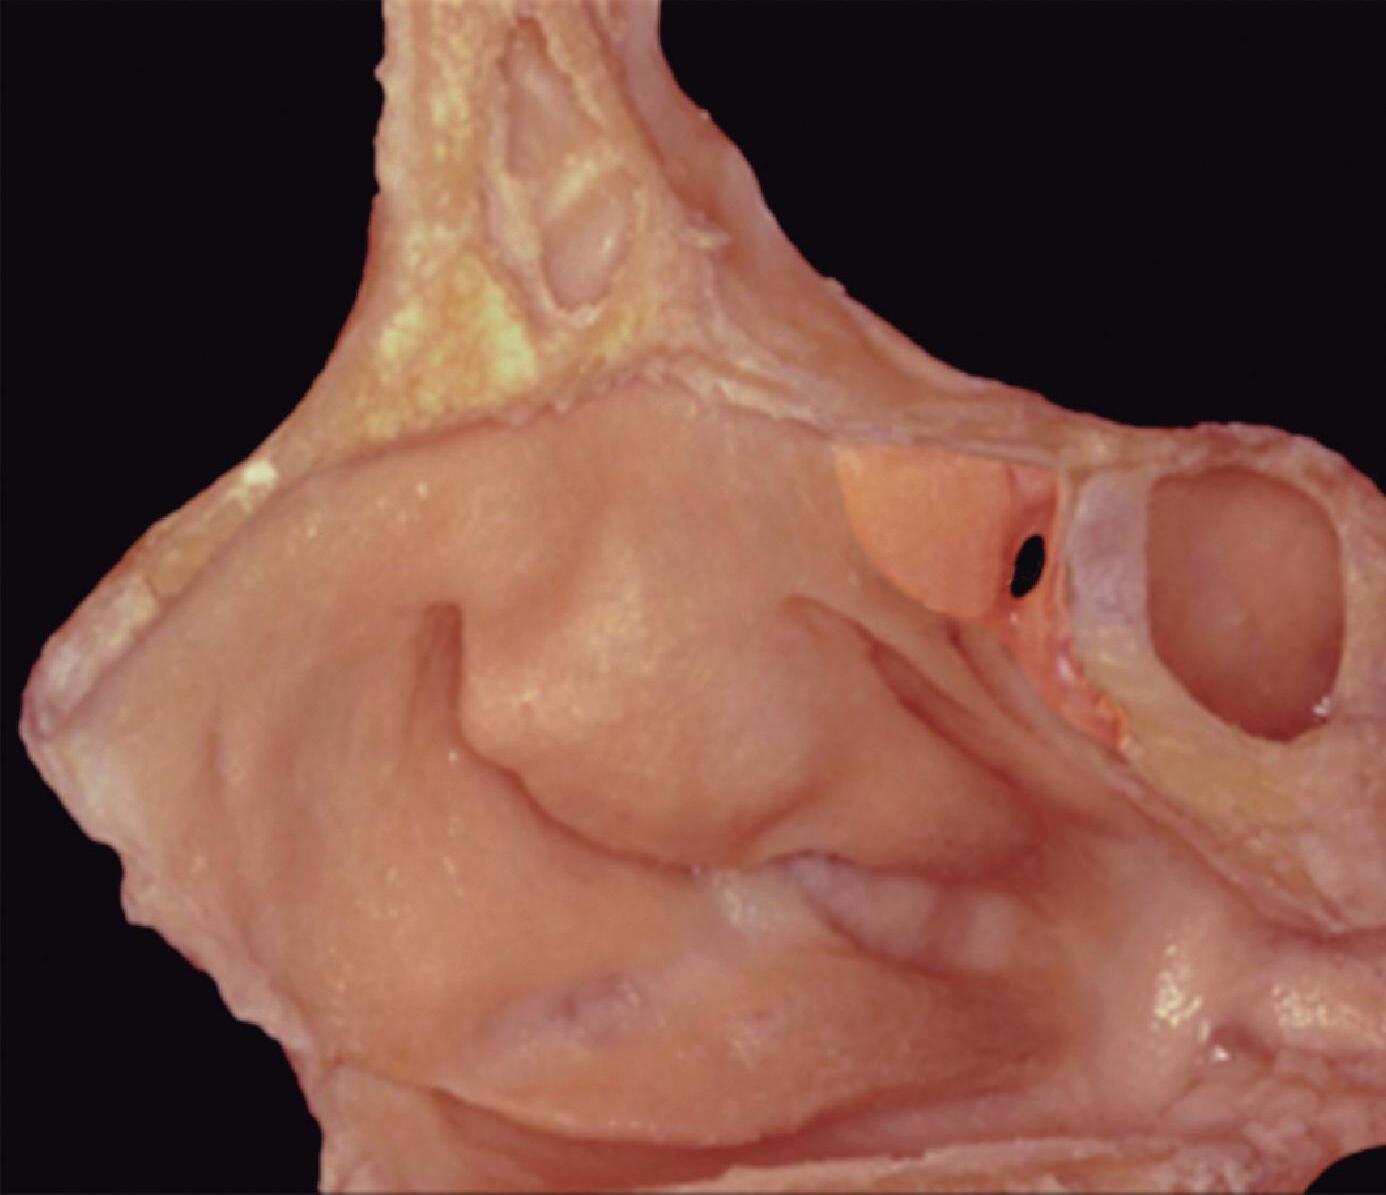

1-13. Montagem em aspecto endoscópico e peça anatômica (Bagatella) demonstrando a relação do processo uncinado e bulha etmoidal com a parede medial da órbita: (1) porção meatal da concha média; (2) processo uncinado; (3) bulha etmoidal; (4) parede medial da órbita.

1-16. Relação da bulha etmoidal com a órbita em corte axial, coronal e sagital, respectivamente.

A bulha etmoidal lembra a forma de uma meia-lua e se encaixa na parede medial da órbita (lâmina papirácea) criando, posterossuperiormente (em sua relação com a porção vertical da lamela basal), um recesso algumas vezes chamado de seio lateral e outras de recesso suprabulhar, onde se abrem a própria bulha e cavidades etmoidais vizinhas.